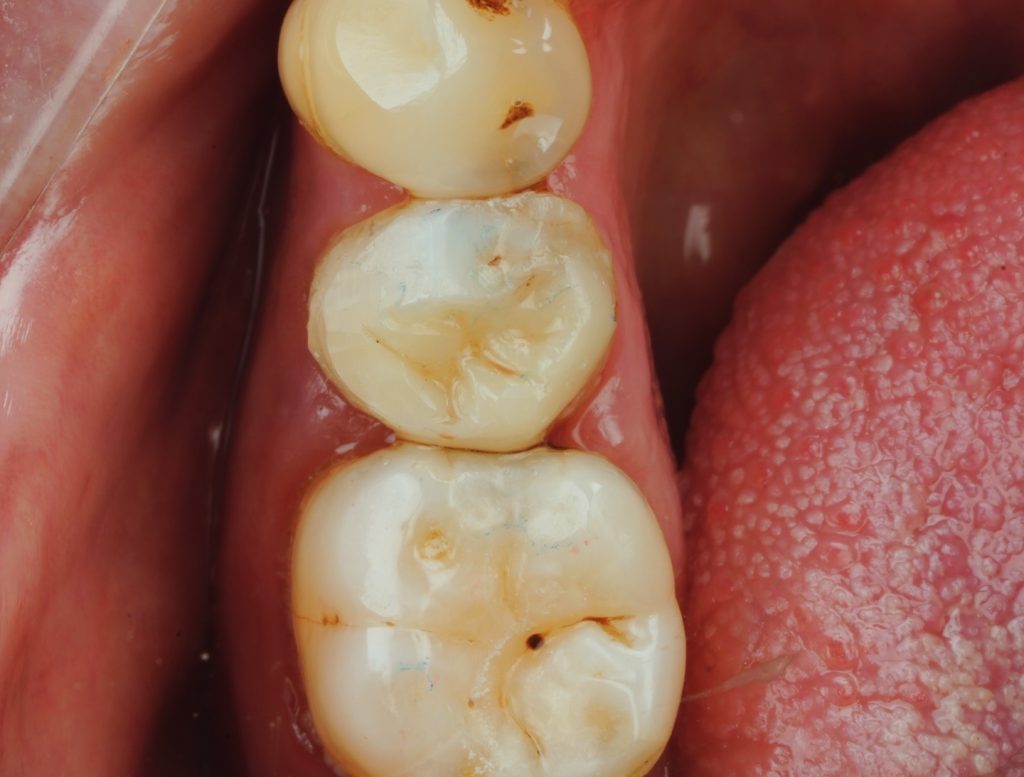

Incremental layering of Tokuyama Estelite Sigma Quick (A2) recreated natural cusp inclinations. Each increment (≤2 mm) was sculpted anatomically and light-cured 40 s per surface under the microscope. Final morphology mimicked the premolar’s functional ridges (Fig 6).

The final restoration showed ideal contour, proximal contact, and occlusal harmony (Fig 8). Radiographic review confirmed dense obturation and perfect coronal seal. At 1-month follow-up, the tooth remained asymptomatic and functional.

- Fig 6: Cuspal-coverage layering with Tokuyama Estelite Sigma Quick.

- Fig 8: Final radiograph and clinical outcome showing functional integration.